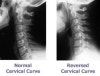

정상 성인은 C3 높이 위치에서 척추 전방 연부조직의 폭이 C3 경추체 폭의 1/3을 넘지 않습니다. 근육경직으로 경추의 굴곡 곡선이 일자가 되거나 반전될 수 있지만, 이는 정상인의 약 10% 정도에서도 나타날 수 있습니다. 나이가 많을수록 경추에서 퇴행성 변화가 보이며 C56와 C67에서 흔히 나타납니다.